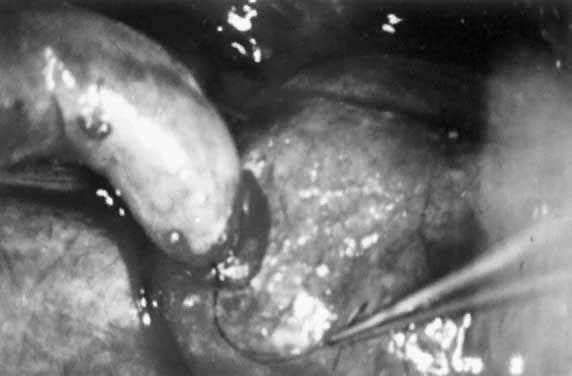

The surgical treatment of cornual occlusion by uterotubal implantation has been replaced by cornual-isthmic reanastomosis because of its superior postreversal pregnancy rates of 46% to 69%.23,24,25,26,27,28 The technique involves preparation of the isthmic portion of the tube similar to that with isthmic-isthmic reanastomosis, with some modification of the cornual side. With a small blade, such as a no. 15 Bard-Parker scalpel, the cornual region is shaved serially. One-millimeter slices are removed until patency is shown (Figs. 7 and 8). Bleeding areas are controlled, preferably by microbipolar cautery, to minimize tissue injury. After the stay sutures of 6-0 Vicryl are placed to align the lumens, a two-layer reanastomosis is performed (Fig. 9). A splint is used, but it is removed at the end of the procedure. A cornual-ampullary reanastomosis is more difficult than a cornual-isthmic procedure because of the large discrepancy in lumen diameter of the ampulla. The best recommendation is to make the ampullary diameter as small as possible, as recommended for the isthmic-ampullary reanastomosis.

Fig. 9. Cornual-isthmic reanastomosis. The first layer is completed.(Courtesy of Marvin Yussman, MD.)